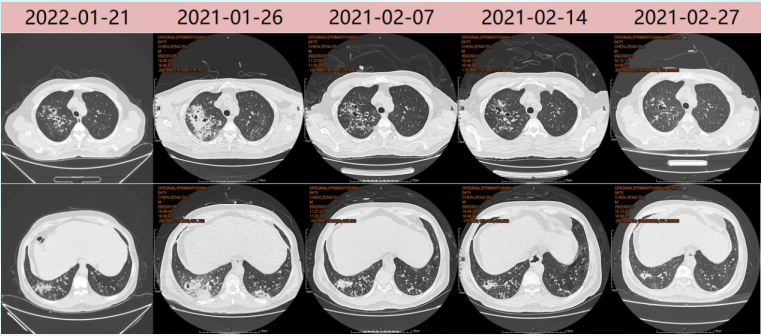

胸部CT(2022-01-20):结节影,树芽征,支气管壁增厚(图13)

图片

13  病例3胸部CT